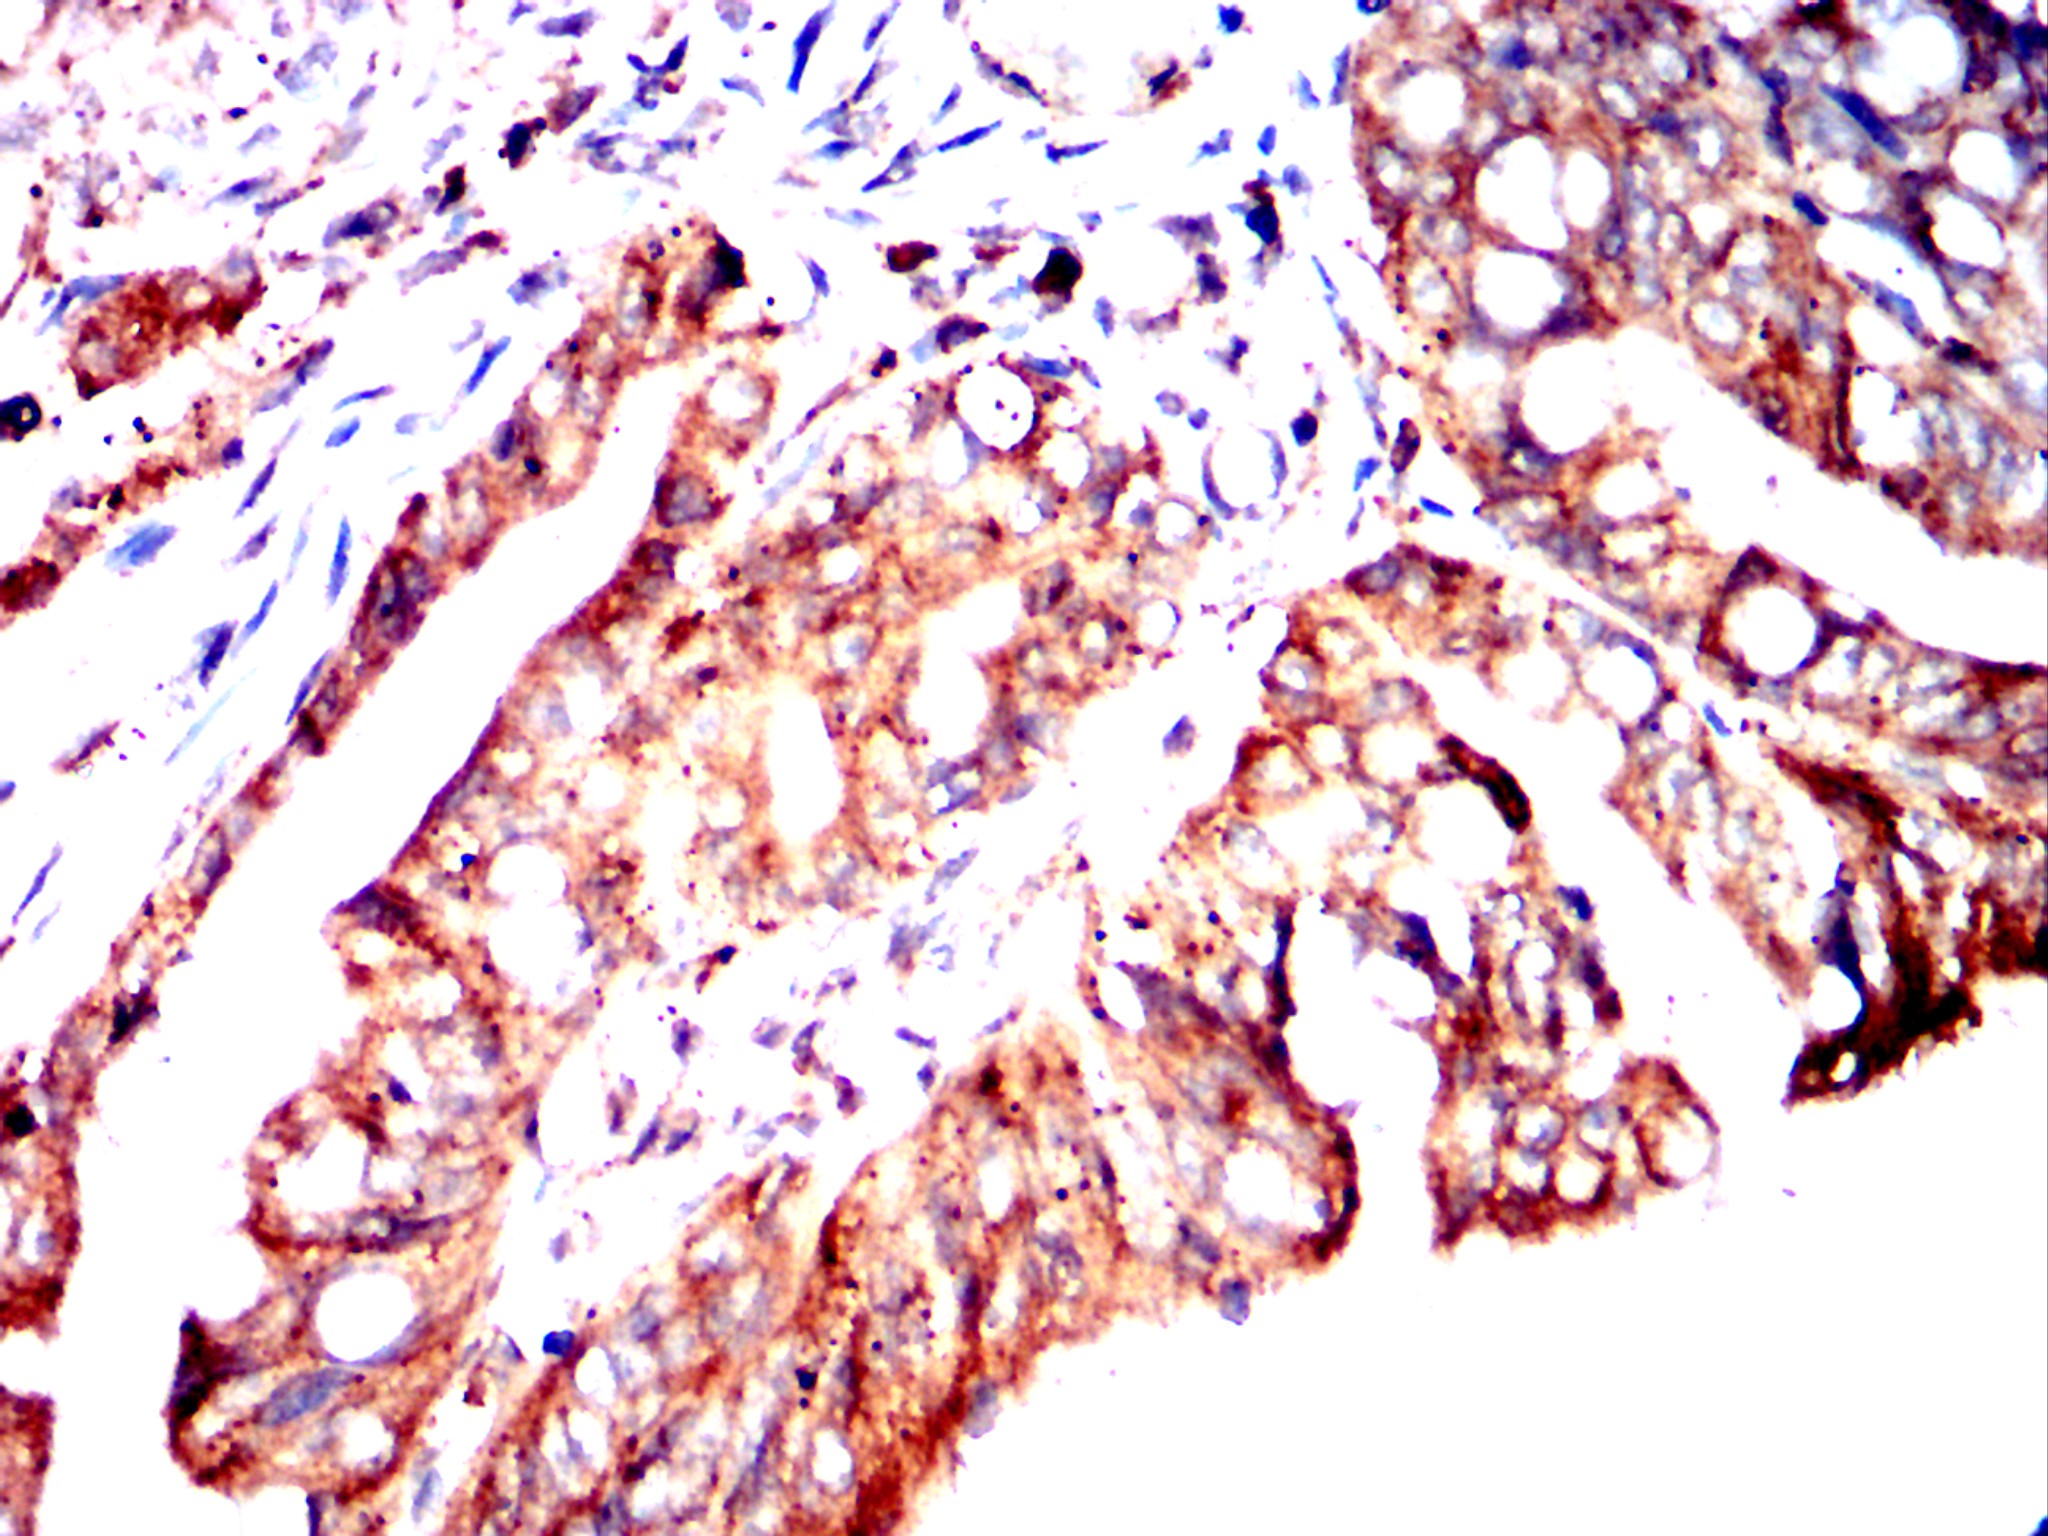

Immunohistochemical analysis of paraffin-embedded human cervical cancer tissues using CHRM3 mouse mAb with DAB staining.

-

Immunohistochemical analysis of paraffin-embedded human rectal cancer tissues using CHRM3 mouse mAb with DAB staining.